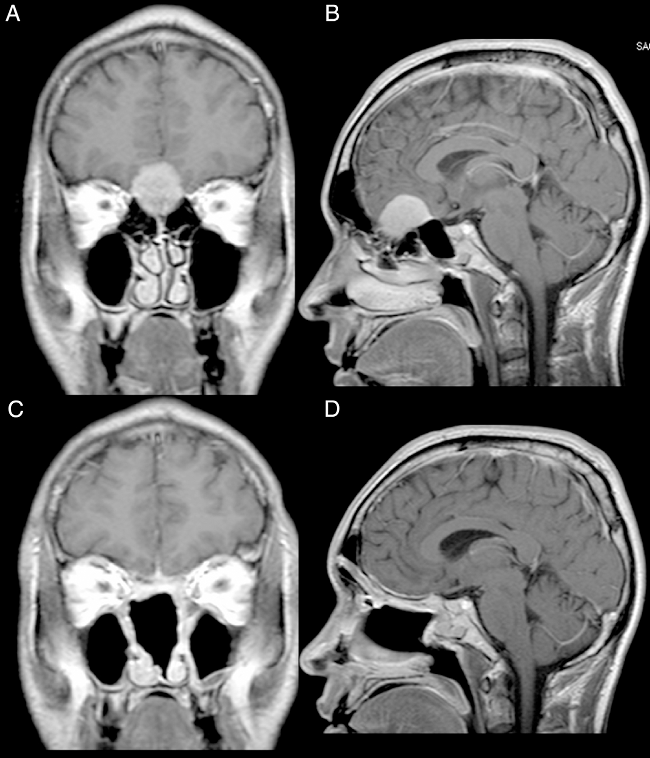

Female, 49 years old, complaining of diminished olfaction and cognitive changes (periods of disorientation and confusion and memory impairment). Magnetic resonance imaging (MRI) showed a large intracranial mass, with dural attachment and tail on top of the cribriform plate, occupying most of the anterior skull base with significant mass effect and oedema in both frontal lobes (Fig. 1).

Male, 39 years old, complaining of mild to moderate frequent headaches and diminished olfaction. MRI showed an intracranial mass with dural attachment on top of the cribriform plate with bone invasion of the plate and the ethmoid (Fig. 2).

Both patients had anosmia after the procedure as expected for a transcribriforme approach, but were free of recurrence and without any signs of brain herniation through the bone defect on magnetic resonance imaging (Figs. 1,2 and 6).